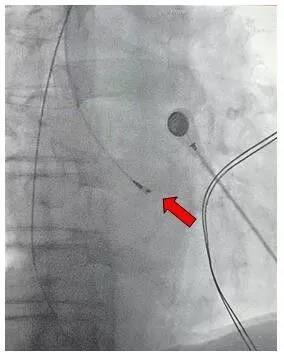

右前斜 30°X 线透视下,调控指引导管使其头端接近并指向希氏束部位。(红色箭头所示)

通过特殊尾线连接到电生理记录仪,标测到希氏束电位。(红圈所示)